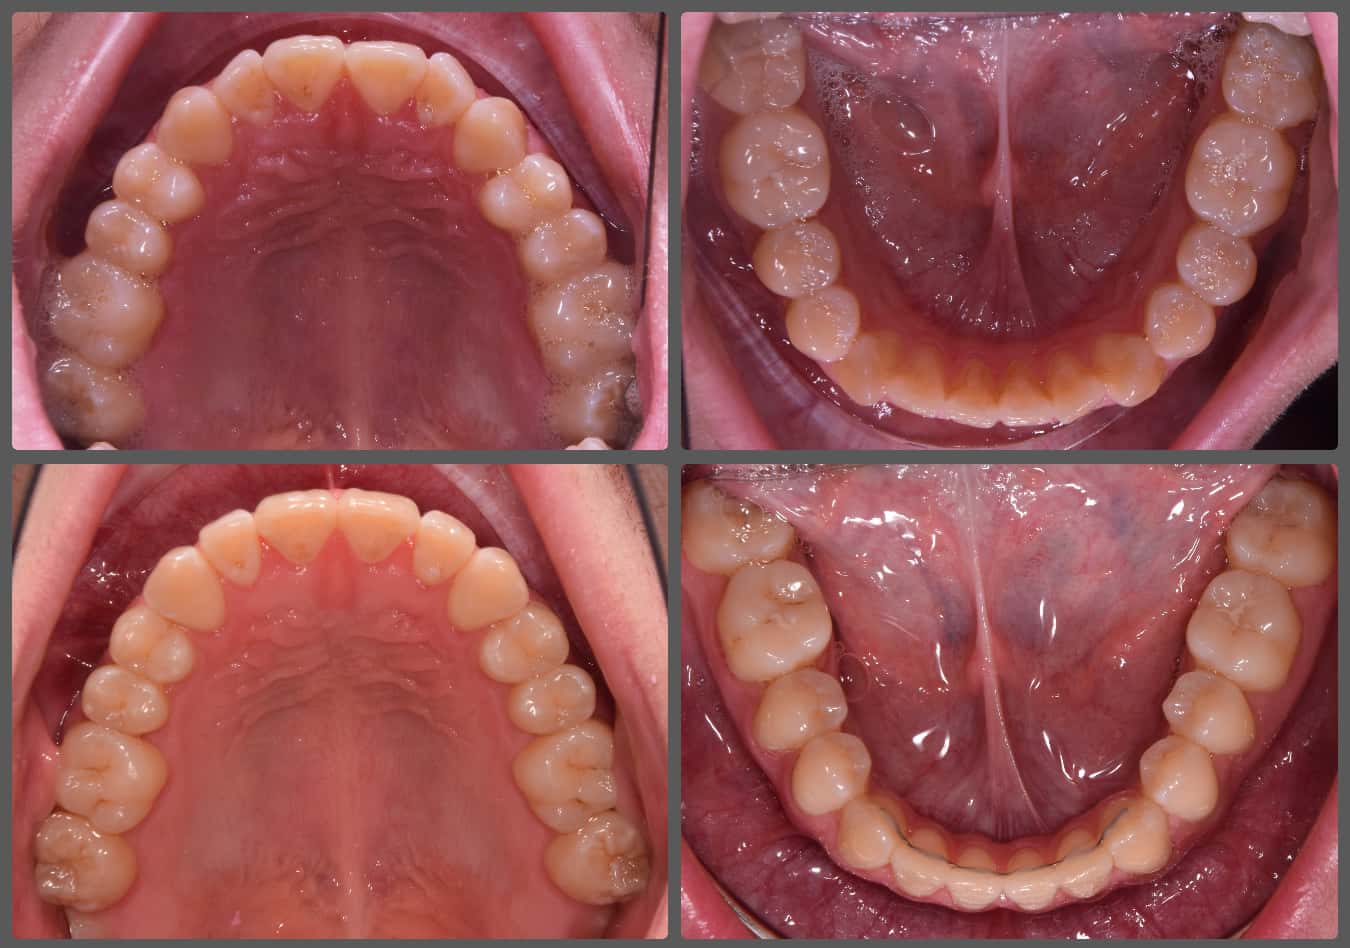

Balázs súlyos alsó torlódása miatt keresett fel magánrendelésemen. A diagnosztikus vizsgálatok során előbbin túl alsó-felső fogívszűkületet, valamint nyitott harapási hajlamot állapítottam meg. Kezelését Pitts21 alsó-felső rögzített fogszabályozó készülékkel kezdtük meg. A nyitott harapási hajlamot a hátsó fogakra helyezett harapásemelővel kontrolláltuk. A torlódott fogaknak tolórugóval és interproximális redukcióval teremtettünk helyet, és intermaxilláris gumihúzással tökéletesítettük a harapást. A fogszabályzó kezelés teljes időtartama alatt Balázs 110%-osan együttműködő volt, ezért 21 hónap alatt sikerült kiemelkedő végeredményt elérnünk.